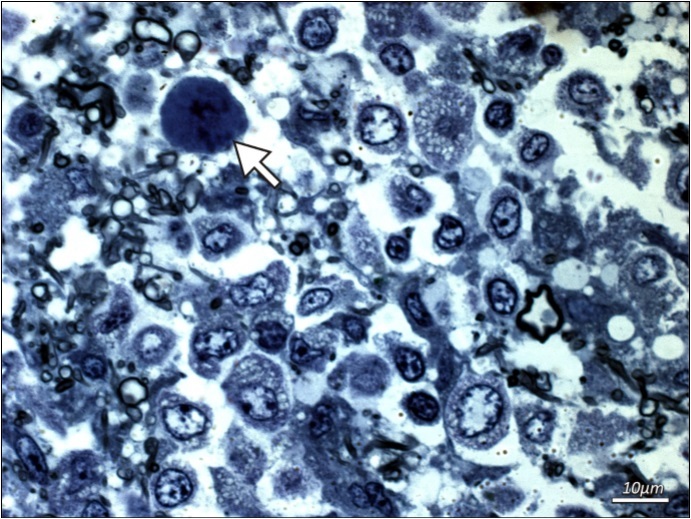

Additional examinations of post-mortem biopsy material taken from subcortical white matter (frontal and temporal lobe regions) by light microscopy LM and transmission electron microscopy TEM were performed. LM analysis of semi-thin sections confirmed the presence of demyelinating foci in the white matter region. Oligodendroglial cells that represent the main site of active JVC infection were found to have structural abnormalities. Particularly notable were enlarged nuclei of these cells and the presence of intranuclear inclusion bodies (Figure 2 and Figure 3). No lymphocytic infiltrations were found in the pathologically altered tissue. Electron microscopy only demonstrated slight post-mortem changes that developed during the 8-hour period between the patient’s death and the fixation of brain tissue. This enhances the value of the TEM results that showed inclusion bodies, i.e. aggregates containing nucleoproteins and virus-like bodies. The structures were located within interchromatin spaces in large oval-shaped oligodendroglial nuclei. The nuclear envelope had numerous isolated scattered enveloped viruses. High microscopic magnification (30-60,000 x) identified an electron-dense centre as viral DNA and an electron-lucent envelope as most likely protein capsid. The viral particles were round in shape, measuring 35-45 nm, and exhibited essentially no variation in shape or size. No fibre (rod) forms were observed. Virus-like particles were also present in the usually narrow strip of cytoplasm, however they were capsid-free.

Figure 2.Additional examinations of post-mortem biopsy material - light microscopy. Subcortical white matter from a patient with PML (routine blue-toluidine staining). Enlarged naked hyperchromatic nucleus of oligodendroglial cell infected with the polyomavirus (arrow) is demonstrated.

Additional examinations of post-mortem biopsy material - light microscopy. Subcortical white matter from a patient with PML (routine blue-toluidine staining). Enlarged naked hyperchromatic nucleus of oligodendroglial cell infected with the polyomavirus (arrow) is demonstrated.